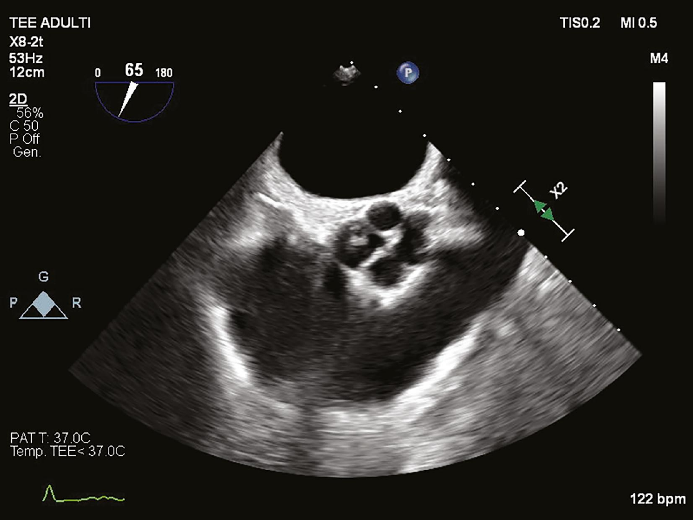

一名 54 岁的女性患者于 2024 年 2 月首次到他们诊所就诊,主诉为劳力性呼吸困难。患者无合并症,否认药物使用和吸烟史。心电图显示患者左心室肥厚。经胸超声心动图示:1)左心室增大,心室壁厚度正常(舒张末期直径 54 mm,室间隔 10 mm,后壁 10 mm,舒张末期容积指数 66 mL/m2); 2)收缩功能保留,舒张功能受损,射血分数 65%,主动脉瓣中心性反流导致重度主动脉关闭不全,主动脉根部和升主动脉尺寸正常,没有其他瓣膜异常。术前经食管超声心动图 (TEE)显示主动脉瓣四叶式畸形,根据 Hurwitz 和 Roberts分型被归类为 A 型,其特征是四个完全相等的瓣叶。计算机断层扫描 (CT) 证实了四叶式主动脉瓣并排除了冠状动脉疾病。